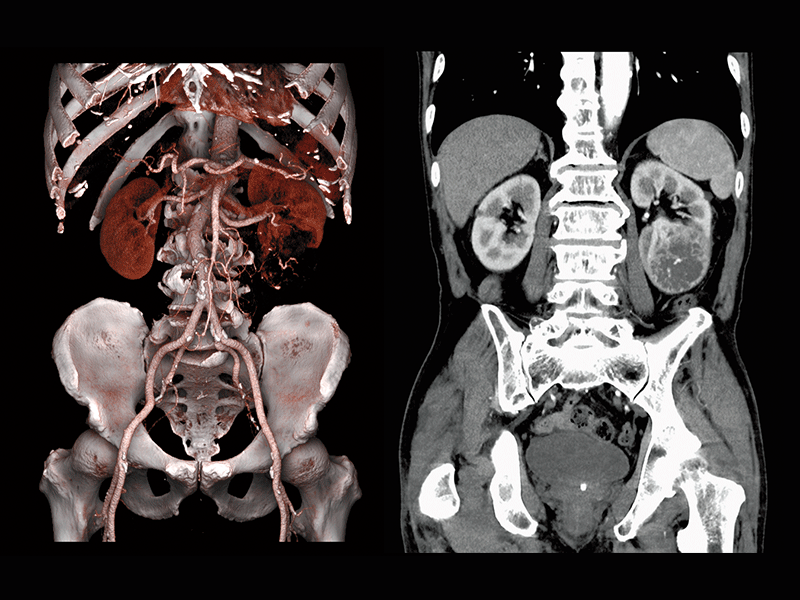

Abdominal aortic occlusion

Intraoperative oxygen desaturation(Left)

Left common iliac artery occlusion(Right)